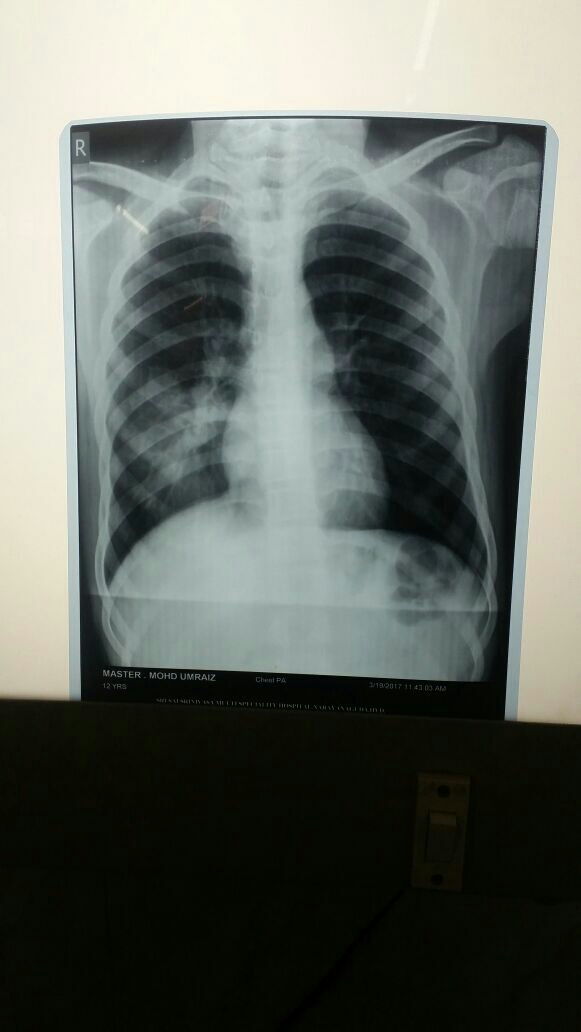

community acquired pneumonia common common in hiv